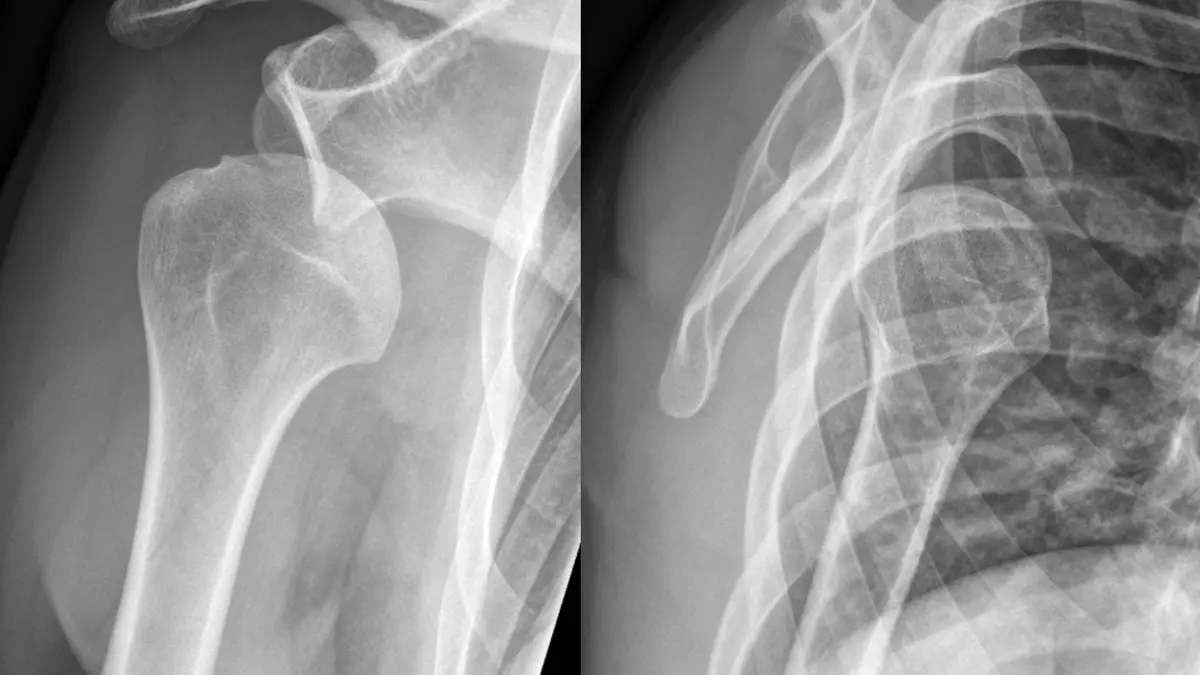

حاجی علیلو سامی در ادامه با توجه به تومورهای بدخیم استخوانی، تصریح کرد: تومورهای بدخیم اصولا در ناحیه زانو با علائمی مانند درد و تورم بروز می یابد.

وی افزود: تومورهای بدخیم بیشتر افراد ۱۰ تا ۲۰ سال را درگیر می کند که برای تشخیص حتما باید نمونه برداری انجام شود که در نهایت پس از تشخیص طی جراحی باید ناحیه درگیر را برداشت و سپس پیوند استخوان انجام داد.

وی افزود: در برخی موارد نیز به جای پیوند می توان از پروتز برای بازسازی استفاده کرد.